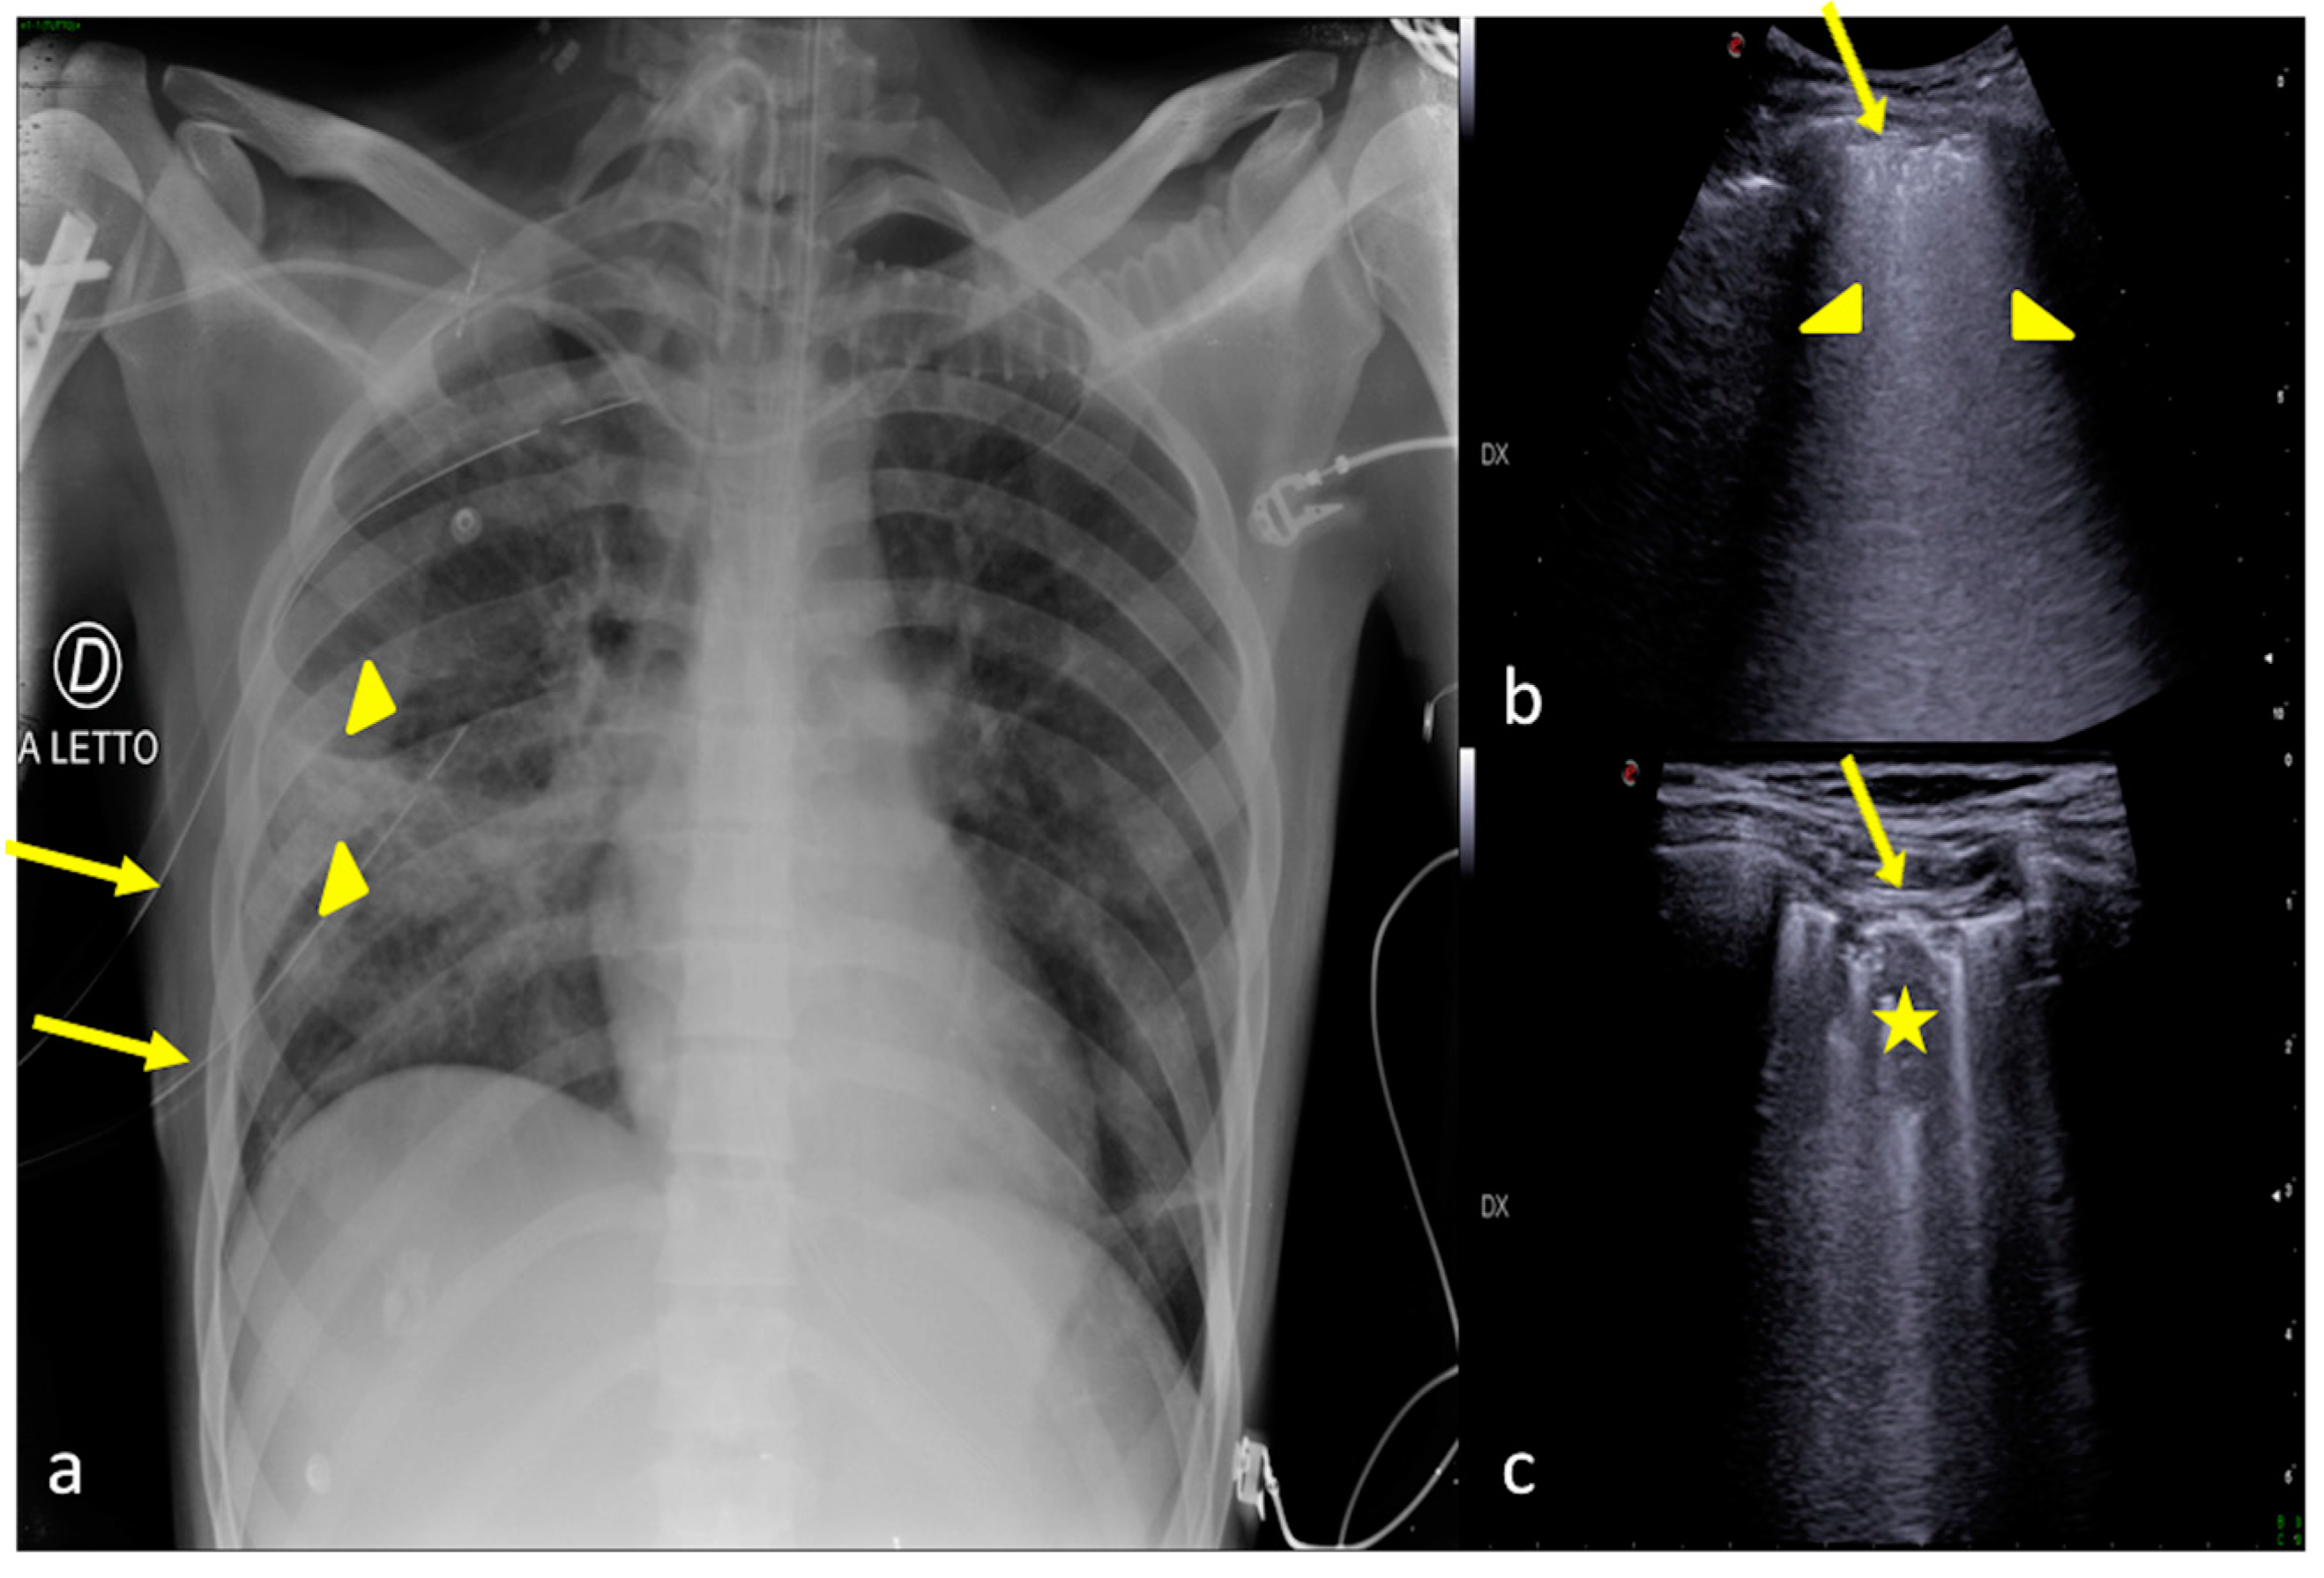

Figure 7.

A 36-year-old female patient admitted to the ICU for a comatose state related to cerebral hemorrhage with fever and dyspnea after endotracheal intubation. Bedside CXR (a) and LUS (b,c). (a) The CXR showed faint areas of decreased parenchymal transparency in the right and left inferior pulmonary field (a, arrowheads); (b). LUS confirmed the consolidative areas at the lung basis (b,c, arrowheads) with hyperechogenic spots as signs of an air bronchogram (b,c, arrows) that moved in line with the respiratory excursion. The clinical scenario and imaging findings were suggestive of phlogistic bronchopneumonia.

Figure 8.

A 26-year-old male patient admitted to the ICU for a comatose state related to high-energy trauma due to a car accident. Bedside CXR (a,c) and LUS (b). (a) The CXR on the day of admission into the ICU showed normal lung expansion with no evidence of parenchymal change. (b) LSU was performed after 24 h endotracheal intubation with the onset of a respiratory worsening and showed an inhomogeneous area of mixed hypoechogenic change at the basis of the left lung (b, arrowhead) with some hyperechogenic spots suggestive of consolidation with an air bronchogram (b, arrow). (c) The CXR confirmed the LUS findings showing an area of reduced diaphony in the basal left field that was considered the manifestation of parenchymal consolidation (c, arrowhead). The clinical scenario and imaging findings were suggestive of phlogistic bronchopneumonia.